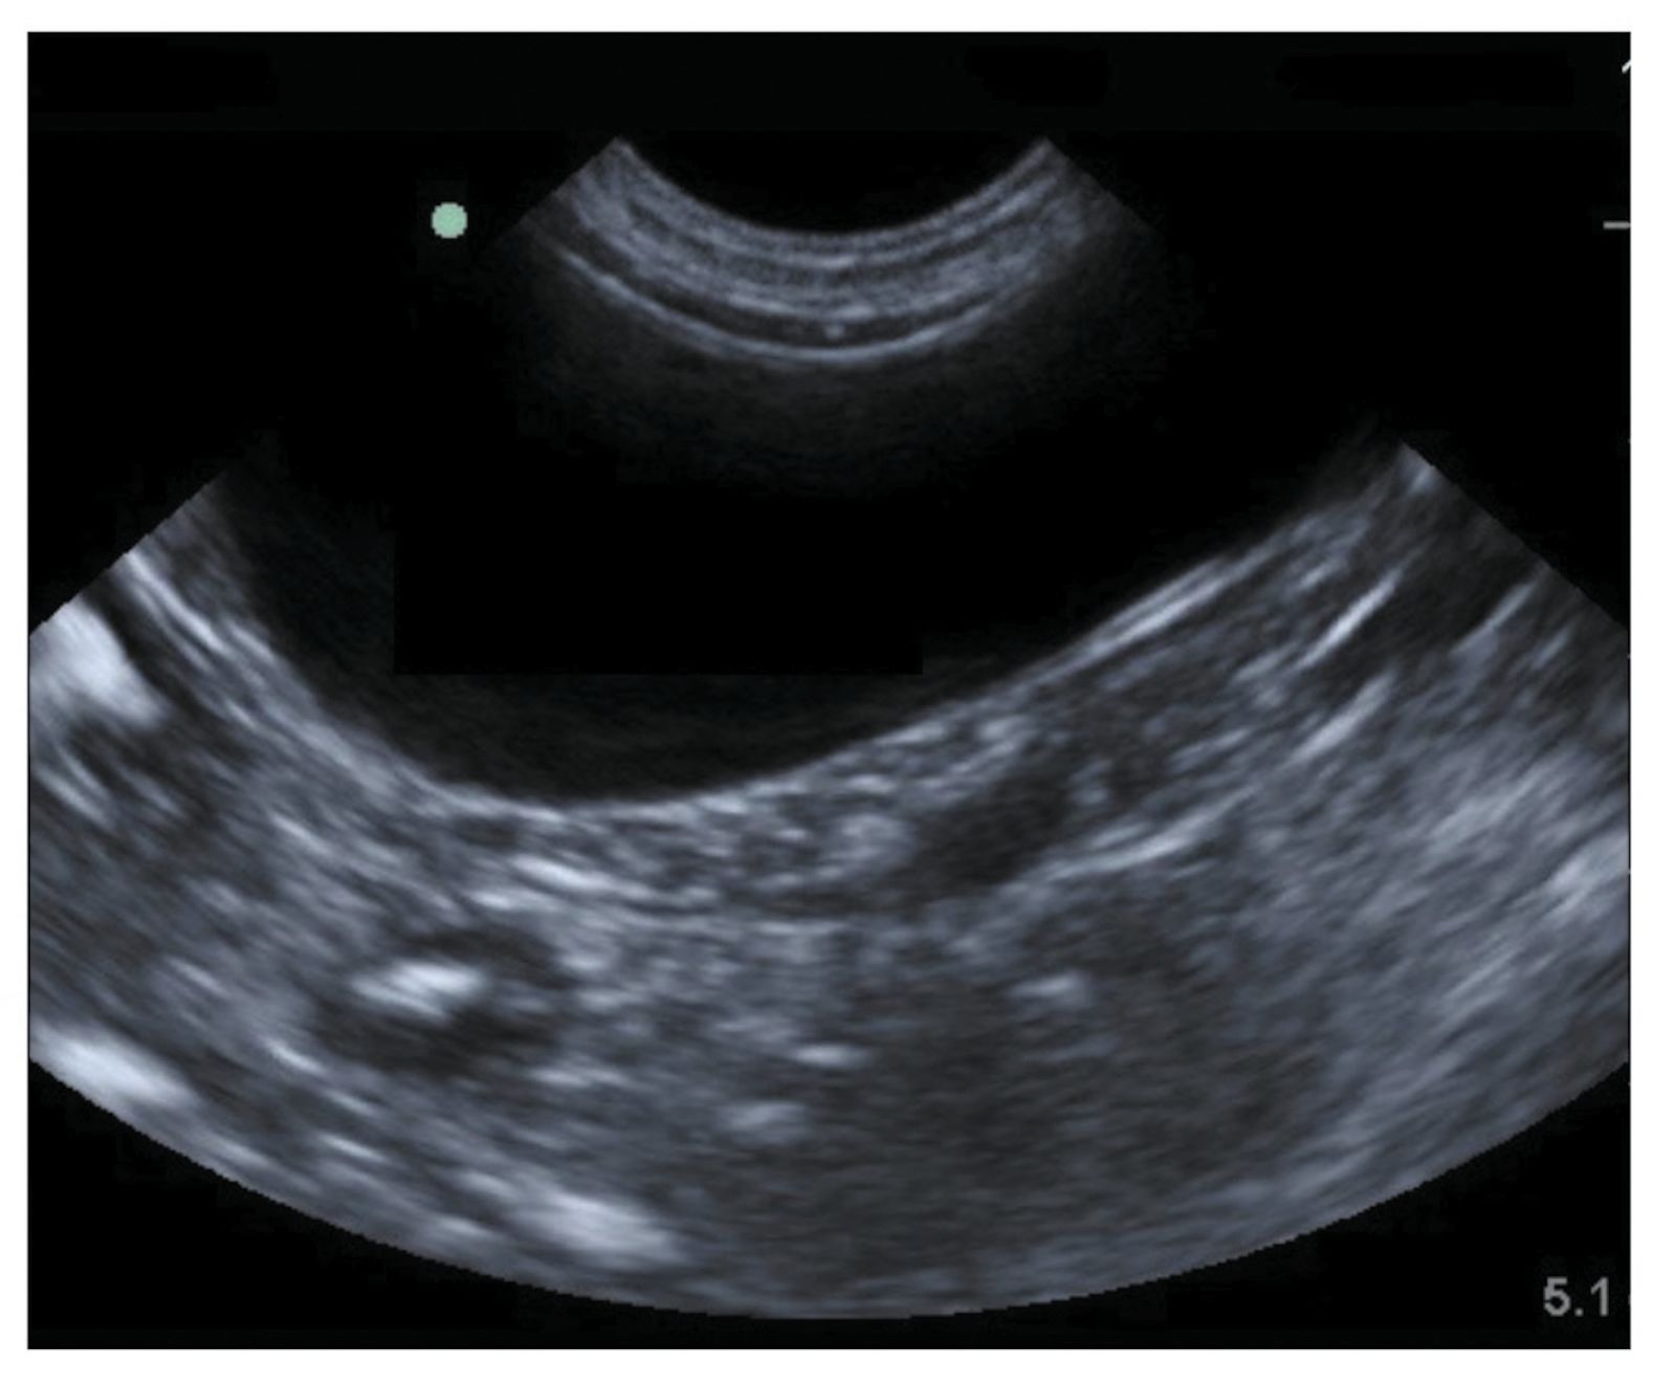

Las imágenes en blanco y negro muestran las estructuras internas de la pelvis como la vejiga y en las niñas los ovarios el útero el cuello del útero o cérvix y las trompas de Falopio. Es posible que le pidan que beba algunos vasos de agua para llenar la vejiga. Si la vejiga se encuentra llena ayuda a visualizar el útero los ovarios la pared de la vejiga y la próstata para el ultrasonido transabdominal. Difícil de valorar porque se producen reverberacio-nes entre la piel y el transductorê 28A veces el colon presiona la vejiga y distorsiona su contorno pudiendo ser confundido con una masa intramu-ralI. A continuación se repite la ecografía para medir la orina residual que queda en la vejiga después de la micción.

Se examina la forma el tamaño y la ubicación de los riñones y también de la vejiga. En caso de que se vayan a estudiar órganos de la pelvis como el útero o la vejiga de la orina conviene beber al menos un litro de agua en la hora previa a la prueba para tener llena la vejiga. Debe esperar hasta que termine el examen para poder orinar. Es indoloro y no produce radiación. Recomendamos que la vejiga está llena.